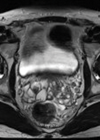

Seminal vesicle calculi

Epidemiology Seminal vesicle calculi are uncommon with just over 100 cases being reported in the literature, although the true incidence is likely to be higher [1-9]. Patients usually present aged between 30 and 45 years old and although the pathogenesis...